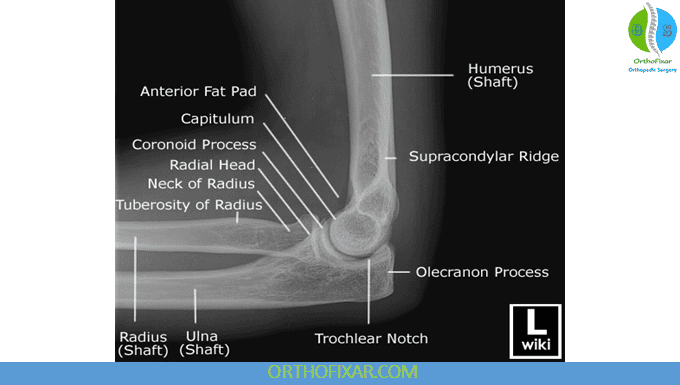

2. Elbow Lateral View (Elbow Flexed at 90°)

Purpose: Complements the AP view by providing a side profile of the elbow, useful for evaluating alignment and soft tissue signs.

Key points to assess:

- Same bony landmarks as in AP view.